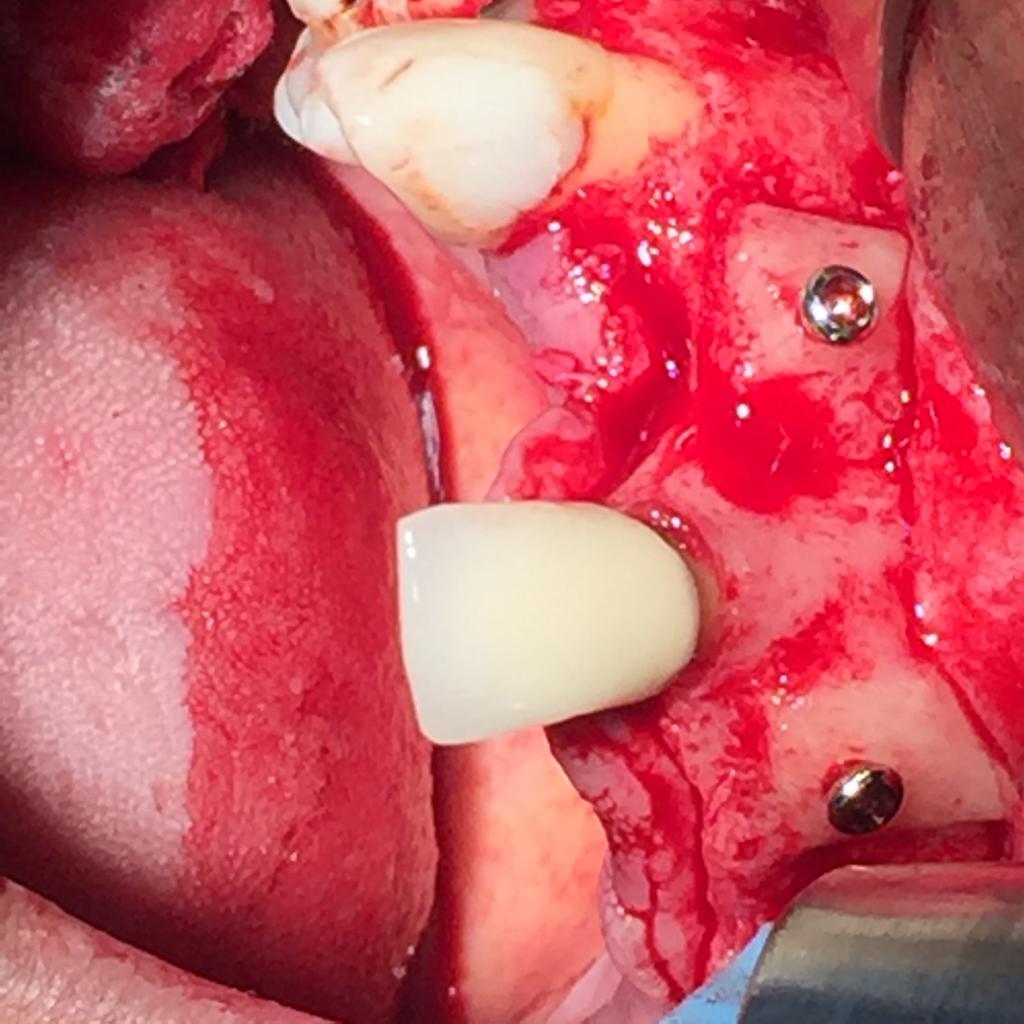

EXPANSION DE CRÊTE